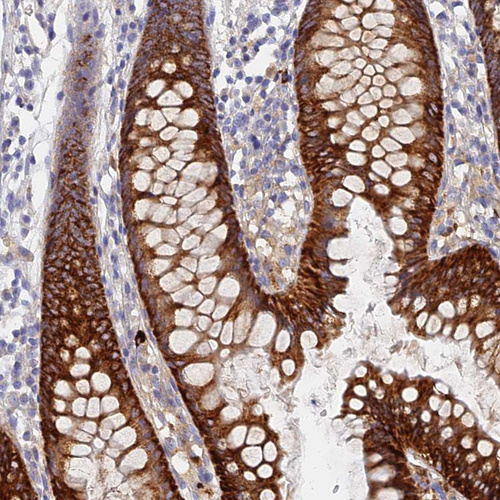

Immunohistochemical staining of human colon shows strong cytoplasmic positivity in glandular cells.